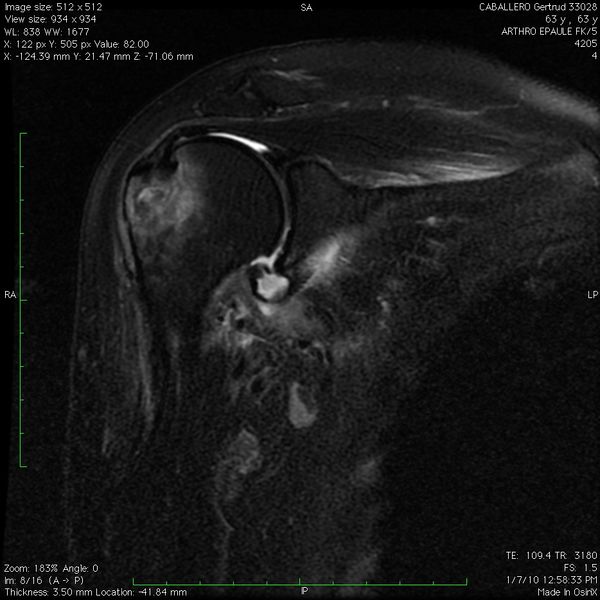

Reverse humeral avulsion of the glenohumeral ligaments (rHAGL)